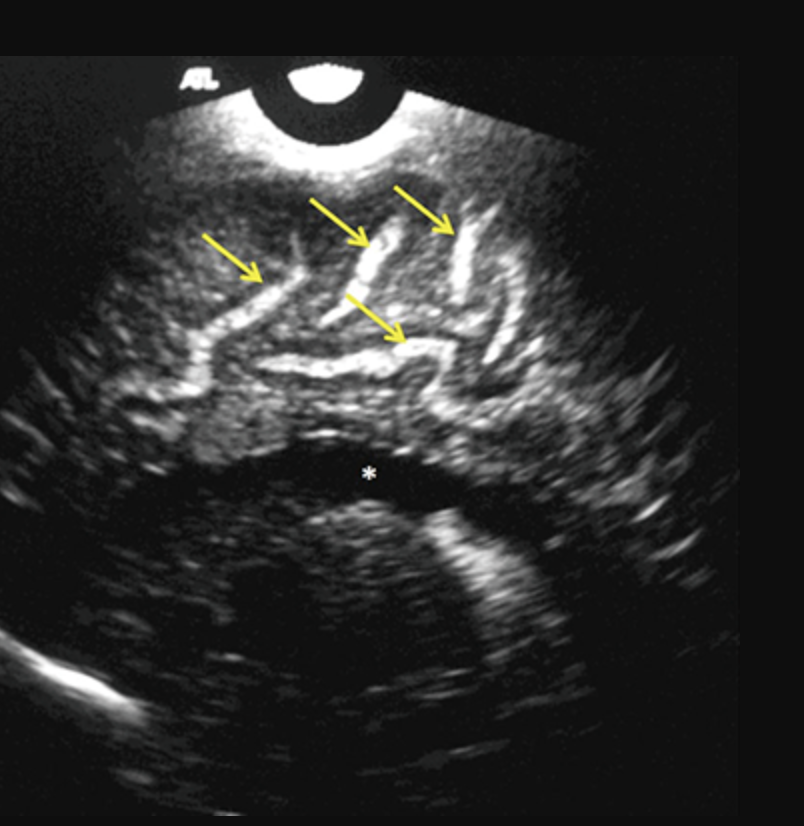

Antenatal ultrasound

With increased availability and quality of antenatal ultrasound, the diagnosis is increasingly made prior to delivery. Antenatal detection is however mostly reported late in pregnancy (3rd trimester).

The dilated median prosencephalic vein (MPV) appears as an anechoic structure in the midline posteriorly and demonstrates prominent flow on Doppler examination. Shunting may lead to complications such as hydrops fetalis or fetal cardiomegaly.